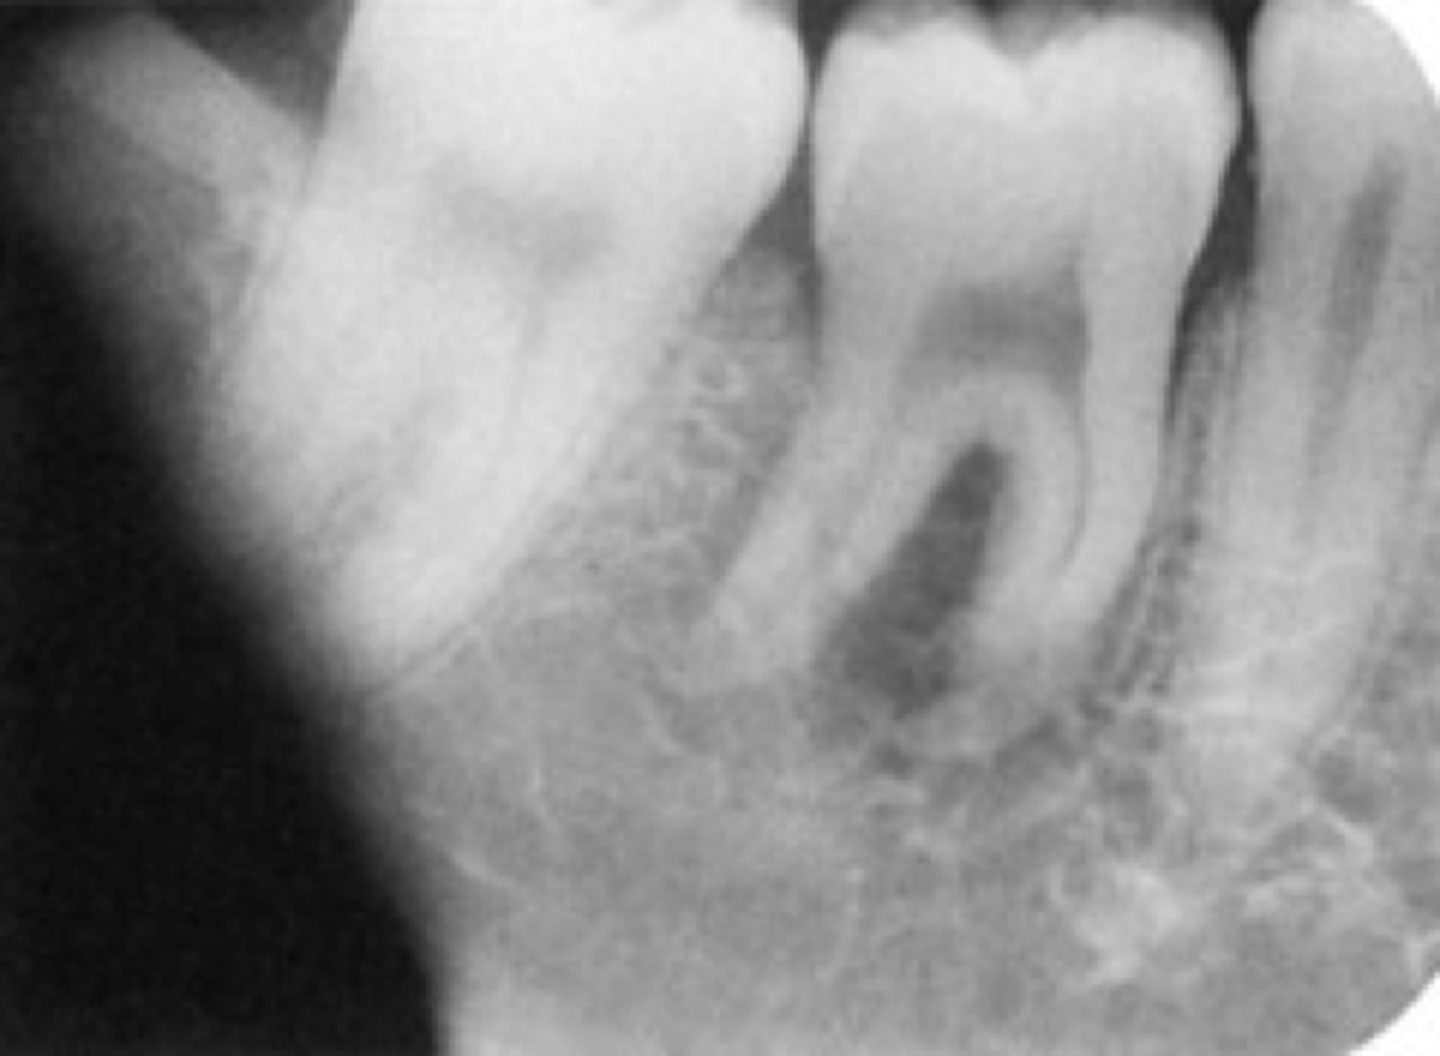

Incorrect Vertical Angulation-->Foreshortened Images

-Teeth appear short with blunted roots

-Vertical angulation was excessive, or too steep, resulting in images that are shorter than the actual teeth

-This occurs more often with the bisecting technique

-To prevent do not use excessive vertical angulation

Tube Head & PID-->Foreshortening of the image

-Excessive angulation (too steep) causing shortening of the anatomy of the teeth and/or cutting off occlusal or incisal edge.

1. PID Too steep Vertical angulation

2. Foreshortening of the image: Excessive angulation (Too Steep)

Foreshortened image; Vertical angulation is too steep, Possible deflected film.